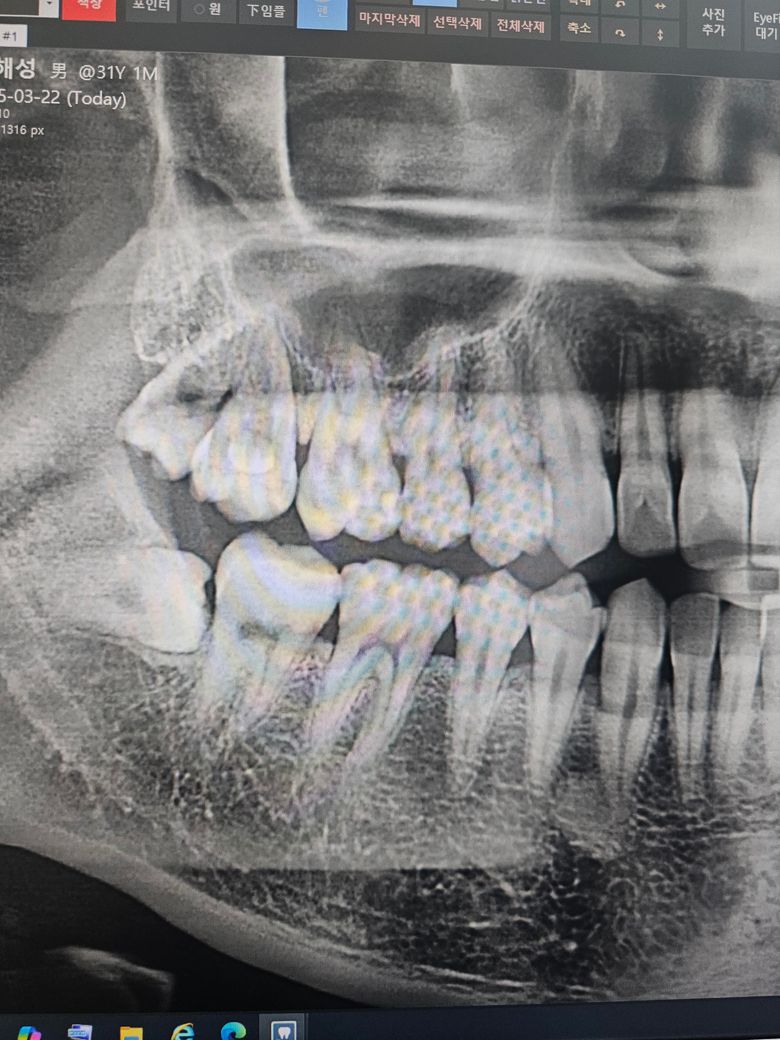

• 2번 째 사진

두번째 치과에서 하신 말씀이랑 다들 비슷한 의견일꺼에요. 치과의사마다 치료 하는 방법이 다르기 때문에 어떤게 옳다고 말씀드리기가 어렵습니다. 사진상으로 인접면에 충치가 없는건 아니고 의심되는 치아들이 많이 보이긴하니 계속해서 의심이 드신다면 불편한 치아만 치료를 먼저 하시고 나머지는 지켜보시면될것같습니다.

사진으로만 보기에는 큰충치가 보이지는 않습니다.